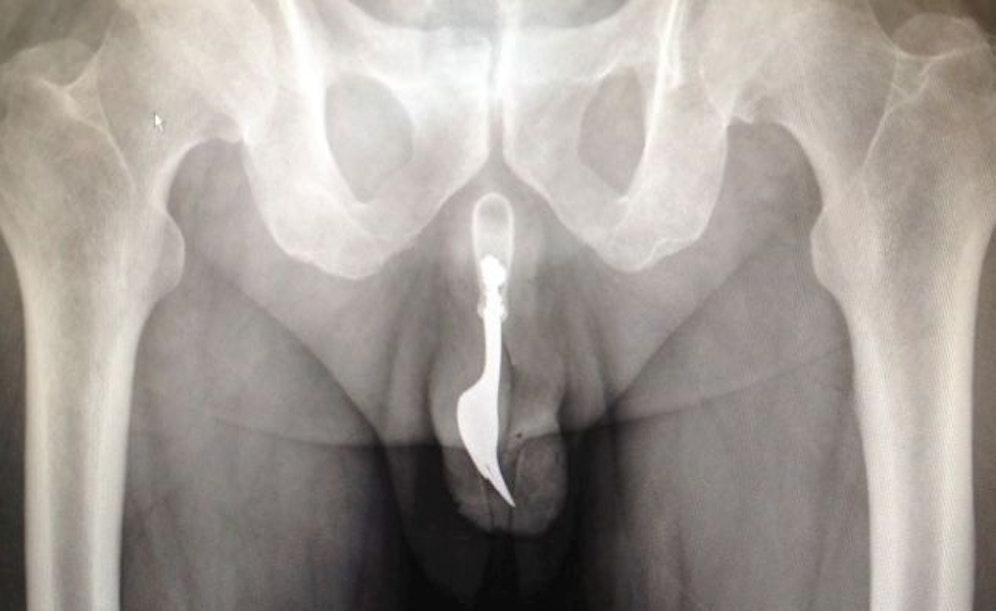

Weil er sich selbst eine Gabel in seinen Penis eingeführt hat, hat ein 70-Jähriger in Australien Erwähnung im Chirurgie-Fachblatt "International Journal of Surgery" gefunden. Der Fall in einem Krankenhaus in Canberra war aus Sicht der Ärzte so ungewöhnlich, dass sie ihn in der aktuellen Ausgabe der Zeitschrift beschrieben.

Der Patient musste sich demnach einer Notfalloperation unter Vollnarkose unterziehen, nachdem er sich zur Selbstbefriedigung eine zehn Zentimeter lange Gabel aus Stahl in seinen Penis eingeführt hatte.

Als der 70-Jährige im Krankenhaus eingetroffen sei, sei die in seinem blutenden Penis steckende Gabel nicht zu sehen gewesen. Die Ärzte hätten mehrere Methoden zur Entfernung des Fremdkörpers erwogen, hieß es in dem Artikel. Schließlich sei die Gabel mit Hilfe einer Zange und "ausgiebiger Einölung" herausgezogen worden.